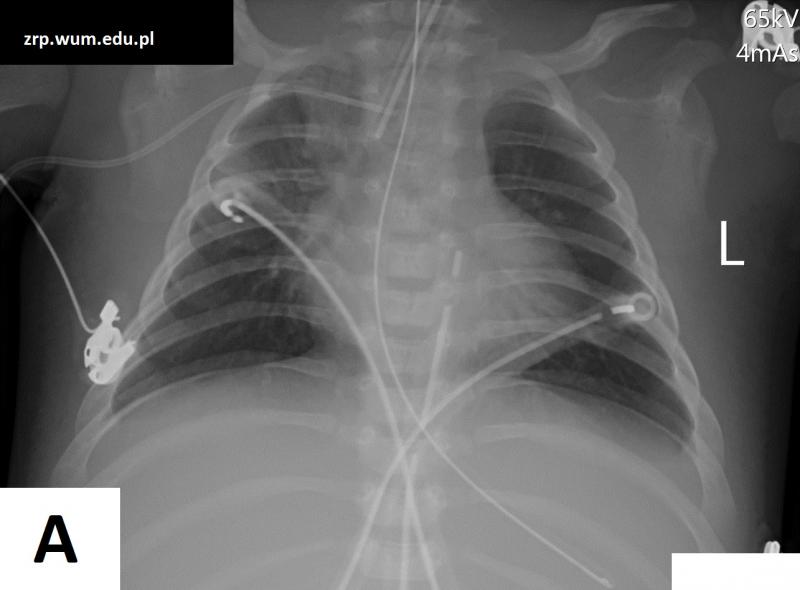

Przypadek 46: Dziewczynka w 1. m-cu życia po operacji kardiochirurgicznej (Tetralogia Fallota), ze znacznym pogorszeniem stanu klinicznego w ciągu kilku godzin.

Rozpoznanie: Wykonano zdjęcia RTG klatki piersiowej w odstępie kilku godzin (wyjściowe - A, i kontrolne - B) - w badaniu kontrolnym znaczne pogorszenie powietrzności płuc - masywne zagęszczenia miąższowe -obraz przemawia za obrzękiem płuc.

Pytanie: Jak różnicuje się obrzęk płuc i zapalenie płuc? Nazwij dreny, cewniki, sondy widoczne na zdjęciach.